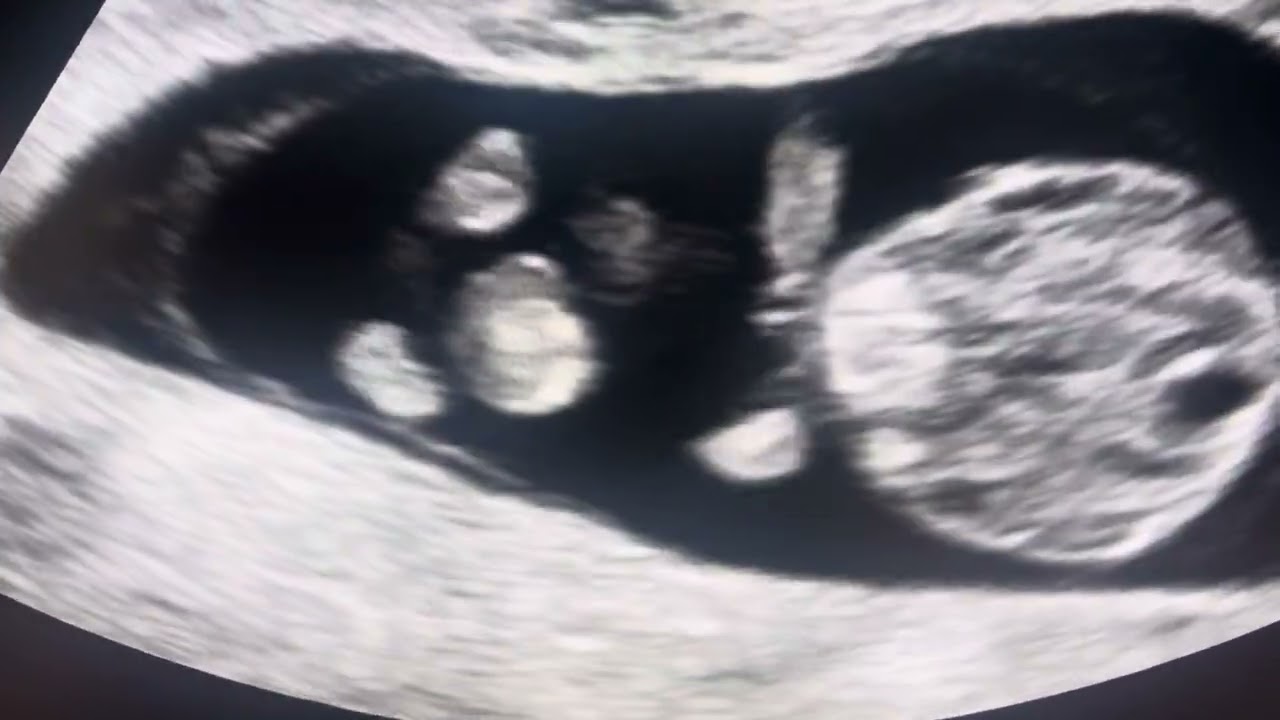

Fetal Midgut Rotation

Описание: Welcome to this enlightening video where we explore the fascinating world of prenatal development. Today, we'll delve into the intricate process of fetal midgut rotation, observable via ultrasound before 12 weeks of gestation. This critical phase of embryonic development not only showcases the complexities of human growth but also highlights the delicate orchestration behind the formation of the digestive system. Join us as we witness the mesmerizing, real-time imagery of the midgut as it takes its definitive shape, a true testament to the wonders of life beginning to unfold. #fetus #baby #pregnant